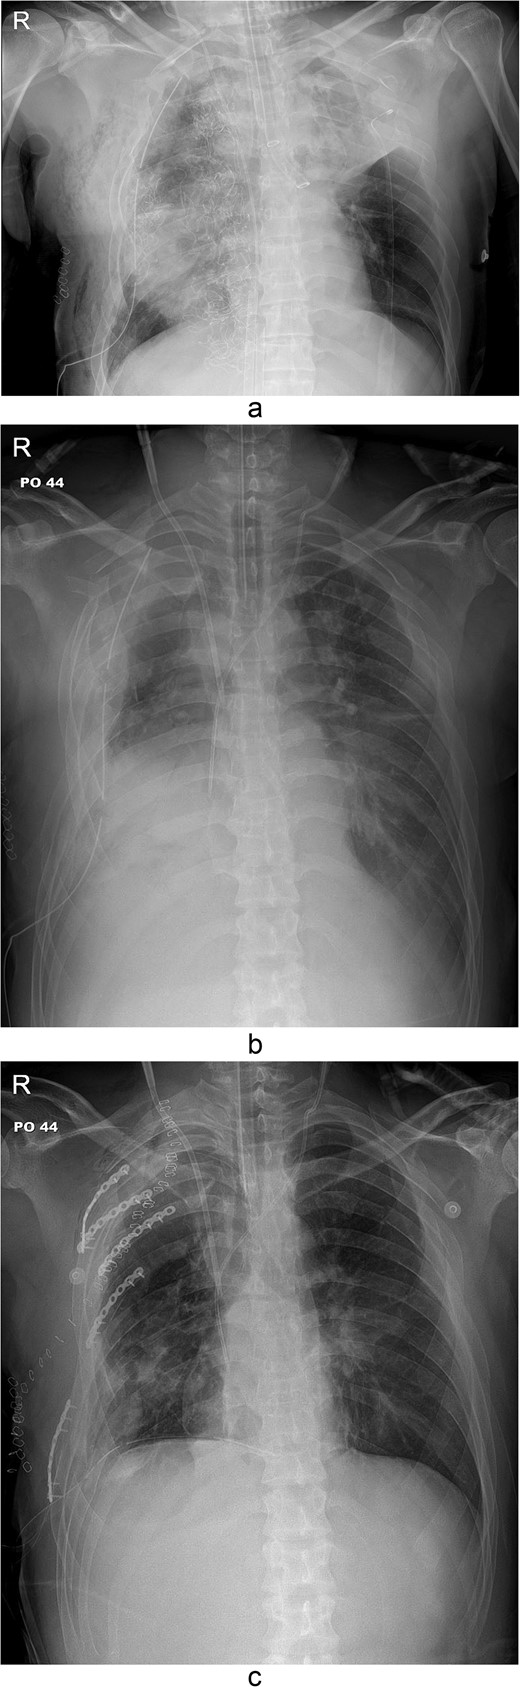

The thoracotomy incision was relatively small, ~8 cm in size, and the intercostal space was not spread to prevent further intraoperative chest wall damage. There were multiple lung lacerations in the upper, middle, and lower lobes with active bleeding. Bloody leakage continued through the avulsed parietal pleura and mediastinum. Hemostasis was achieved by suturing the deeply lacerated lung and packing with gauze (Combat Gauze ™ [Z-Medica QuikClot]) at the chest wall and mediastinum. The operation took 130 minutes. The transfusion of plasma, platelets, and red blood cells was balanced according to the following quantities: 10, 10, and 14 U, respectively. After surgery, the patient was transferred to the intensive care unit (ICU). The PaO2/FiO2 ratio was 52 mmHg with a Positive end expiratory pressure of 15 cm H2O, at a peak inspiration pressure of 30 cmH2O. ABGA showed pH 7.23, pCO2 42, and pO2 47. Veno-venous ECMO based on bilateral femoral vein cannulation was performed (Fig. 3a). Considering the patient’s hemorrhagic predisposition, heparin was not used. Disseminated intravascular coagulation (DIC) occurred along with acute renal failure. Antithrombin III infusion and continuous renal replacement therapy (CRRT) were initiated on the second hospital day. By the 5th day, oxygenation was achieved without ECMO support, followed by decannulation. On the 6th day, the second operation was performed in about 35 minutes. The gauze was removed, and no active bleeding or oozing was seen (Fig. 3b). The third operation, performed on the 13th day, was an open reduction of right ribs 3–7 for correction of flail chest and took 75 minutes (Fig. 3c). After open reduction, the flail chest improved, but the patient was not able to be weaned off the ventilator. Pneumonia and bacteremia developed. A tracheostomy was performed on the 15th day. CRRT was switched to hemodialysis, which was stopped on Day 28. The patient was discharged on the 47th day without tracheostomy. Ten months postoperatively, pulmonary function testing revealed forced expiratory volume in one second and diffusion capacity of carbon monoxide of 77% and 67% of predicted values, respectively. The chest CT and radiographs showed that the lungs had healed well, and there was no displacement of the ribs (Fig. 4). The patient recovered and returned to work.

Chest radiograph and CT scan 10 months after the accident. (a) Chest radiograph showed well-healed fractured ribs and expanded lungs without active lesions. (b)–(e) Non-enhanced axial chest CT images showed recovery from injury.